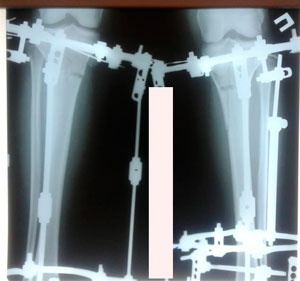

Re: ♥Марина♥

Сообщение Sekretar Onipko »

рентген перед фиксацией аппаратов

Вложения

IMG_7528-03-12-19-12-52.JPG

IMG_7527-03-12-19-12-52.JPG